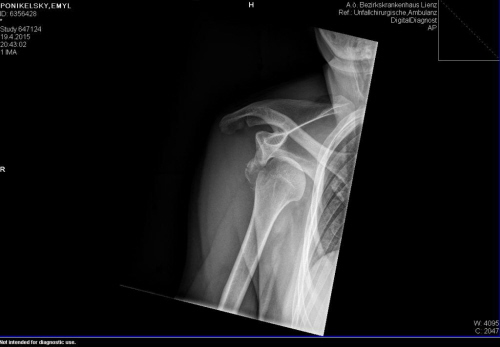

foto by © Emil Ponikelský

V poslední zatáčce mi ustřelily lyže a vylétl jsem do suťoviště. Podřené lyže se velmi rychle zastavily a já letěl dopředu. Následoval bolestivý pád, náraz přilbou do kamení, lyžařské brýle Julbo nevydržely, praskly a schytal to nos. Větší ostrý šutr mne trefil do stehna, další šutr do kolene a batoh mi při pádu vykloubil pravé rameno. Taky jsem se trochu po těch kamenech projel. Výsledek - podřené lyže, roztrhaná gore-tex bunda, roztrhaná softshell bunda, rozbitý foťák a brýle mínus. Zranění - vykloubené rameno, rozdrcený velký hrbol, zlomený nos a poškozený stehenní sval.

Kámoši, co byli se mnou a skupina Čechů co jela po nás mi hned pomohli, následovalo volání na 140. Neposlali vrtulník, ale sanitku z Lienzu na Parkoviště. Všichni mě pak pomohli s fixací, tepelným komfortem a s transportem na parkoviště,. Na parkovišti záchranáři vyhodnotili zranění a volali vrtulník. Pak už jsem se jen 38 minut proletěl a skončil v nemocnici v Lienzu. Kde mě vyšetřili a po 2,5 hodinách od úrazu nahodili rameno zpět. Neskutečná bolest ustoupila. To co je ve vrtulníku a v nemocnici zajímalo nejvíce bylo, zdali jsem členem Alpenverein. Samozřejmě jinak přístup doktorů profesionální a velmi milý. Večer jsem pak podepsal revers a jel s klukama do republiky. Následují den jsem pak už trávil po doktorech a vyšetřeních v ÚVN Praha.